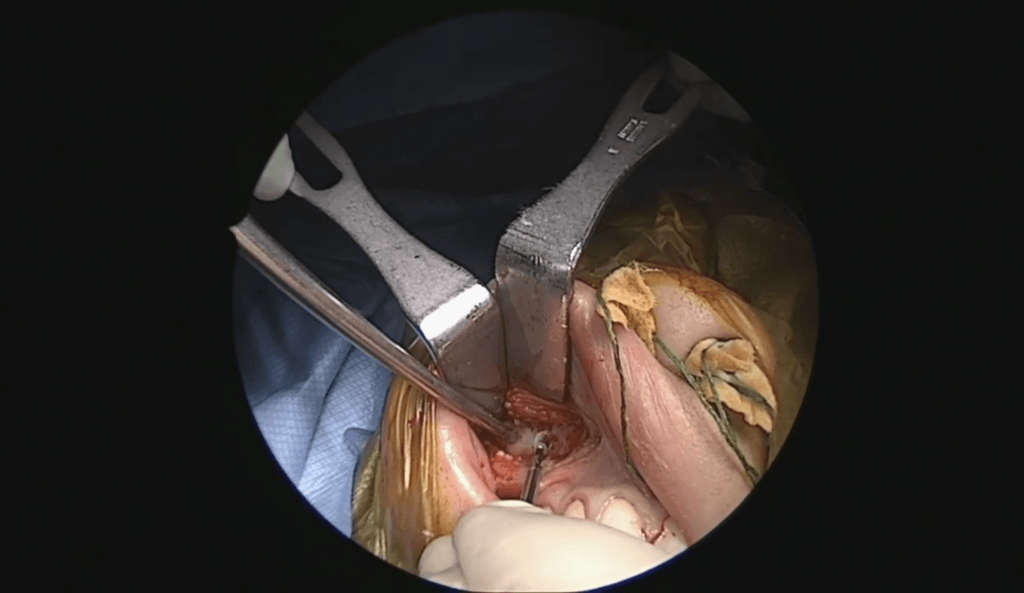

Estapedectomía de revisión con cartílago

El Dr. Sperling realiza una estapedectomía de revisión compleja con retirada de prótesis desplazada y refuerzo cartilaginoso timpánico.